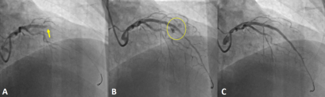

A 63-year-old man with stable angina was scheduled for elective percutaneous coronary intervention of a chronic total coronary occlusion of the right coronary artery (RCA) with epicardial bridging collaterals from the left circumflex artery...

Video Supplement to "Thrombotic Complication After a Double-Barrel Configuration Percutaneous Coronary Intervention in a Chronic Total Occlusion."